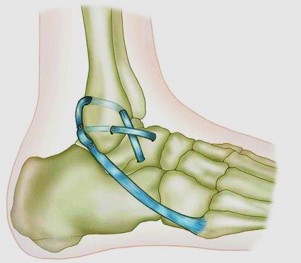

При реконструкции анатомических трансплантатов аутогенные или аллогенные сухожильные трансплантаты помещаются в места прикрепления нативных связок для воссоздания анатомии и механики передней таранно-малоберцовой связки и пяточно-малоберцовой связки. В этих процедурах, трансплантат проходит через туннели в дистальном отделе малоберцовой кости, таранной кости и пяточной кости, чтобы воссоздать как переднюю таранно-малоберцовую так и пяточно-малоберцовую связку (рис.7.2). Трансплантаты сухожилий могут быть фиксированы в кости либо самими швами, либо интерференционными винтами вставленными в костные туннели.

Рис.7.2. Реконструкция передней таранно-малоберцовой и пяточно-малоберцовой связки аутогенными или аллогенными сухожильными трансплантами.